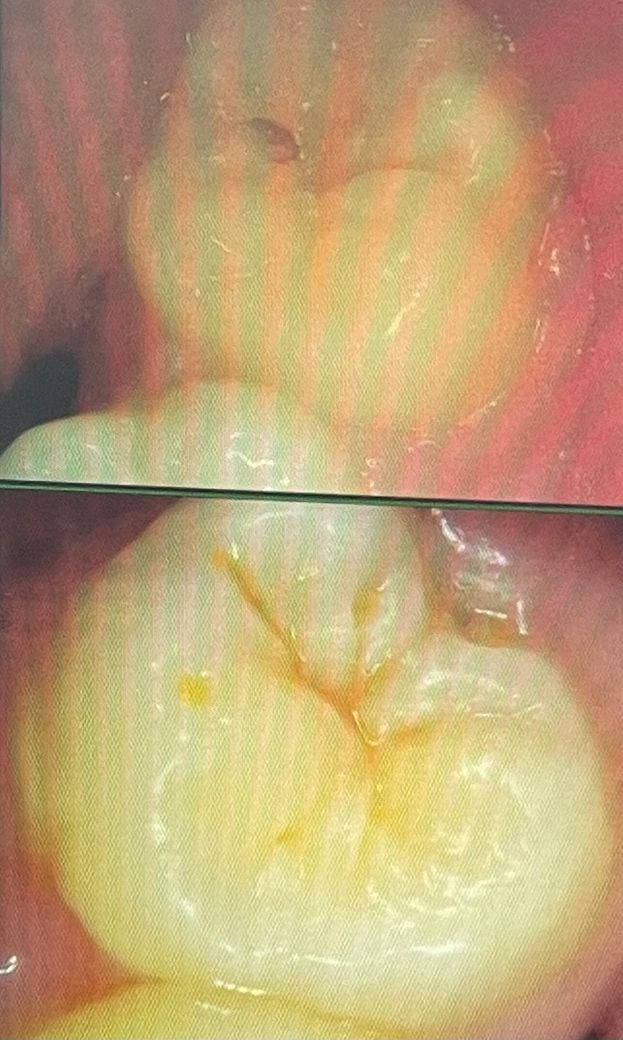

충치 치료해야 하는 수준인지 봐주세요

치과에 갔는데 충치를 전부 레진치료를 해야한다고 하는데요 개당 10만원이라 비용이 부담이 되는데 다른 치과를 한 곳 더 가보기엔 시간이 없어서 질문글 올려요.. 사진 속 치아들이 충치치료를 하지 않는다면 추후 크게 번질까요?

• 1번 째 사진

• 2번 째 사진

사진으로 봤을 경우에는 충치가 심해 보이지 않습니다. 단순한 치아의 착색일 가능성도 있기 때문에 다른 치과에서 더 정확한 확인을 해보는 것이 좋을 것으로 생각됩니다.

충치가 진행이 상당히 되어있는 것으로 보이며 치료를 받으시러 가시는 것이 좋아 보입니다.

초기충치의 상태같습니다 초기충치의 경우 레진으로 치료할 수 있습니다 치과의사에 따라 초기충치는 지켜보자고 하는 경우도 있습니다